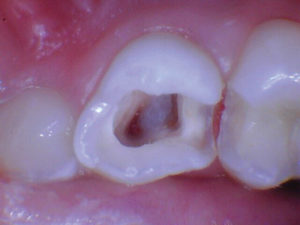

Figura 3. Después de quitar el techo de la cámara pulpar. |

Figura 5. Esta pulpa exhibió una pulpa radicular sana como lo demuestra el sangrado fácilmente controlado. |

Figura 6. Se colocó una capa de 2-3 mm de Biodentine seguida de una capa de Ionoseal (Voco) para evitar el lavado de ATM al proceder con el proceso de restauración. |